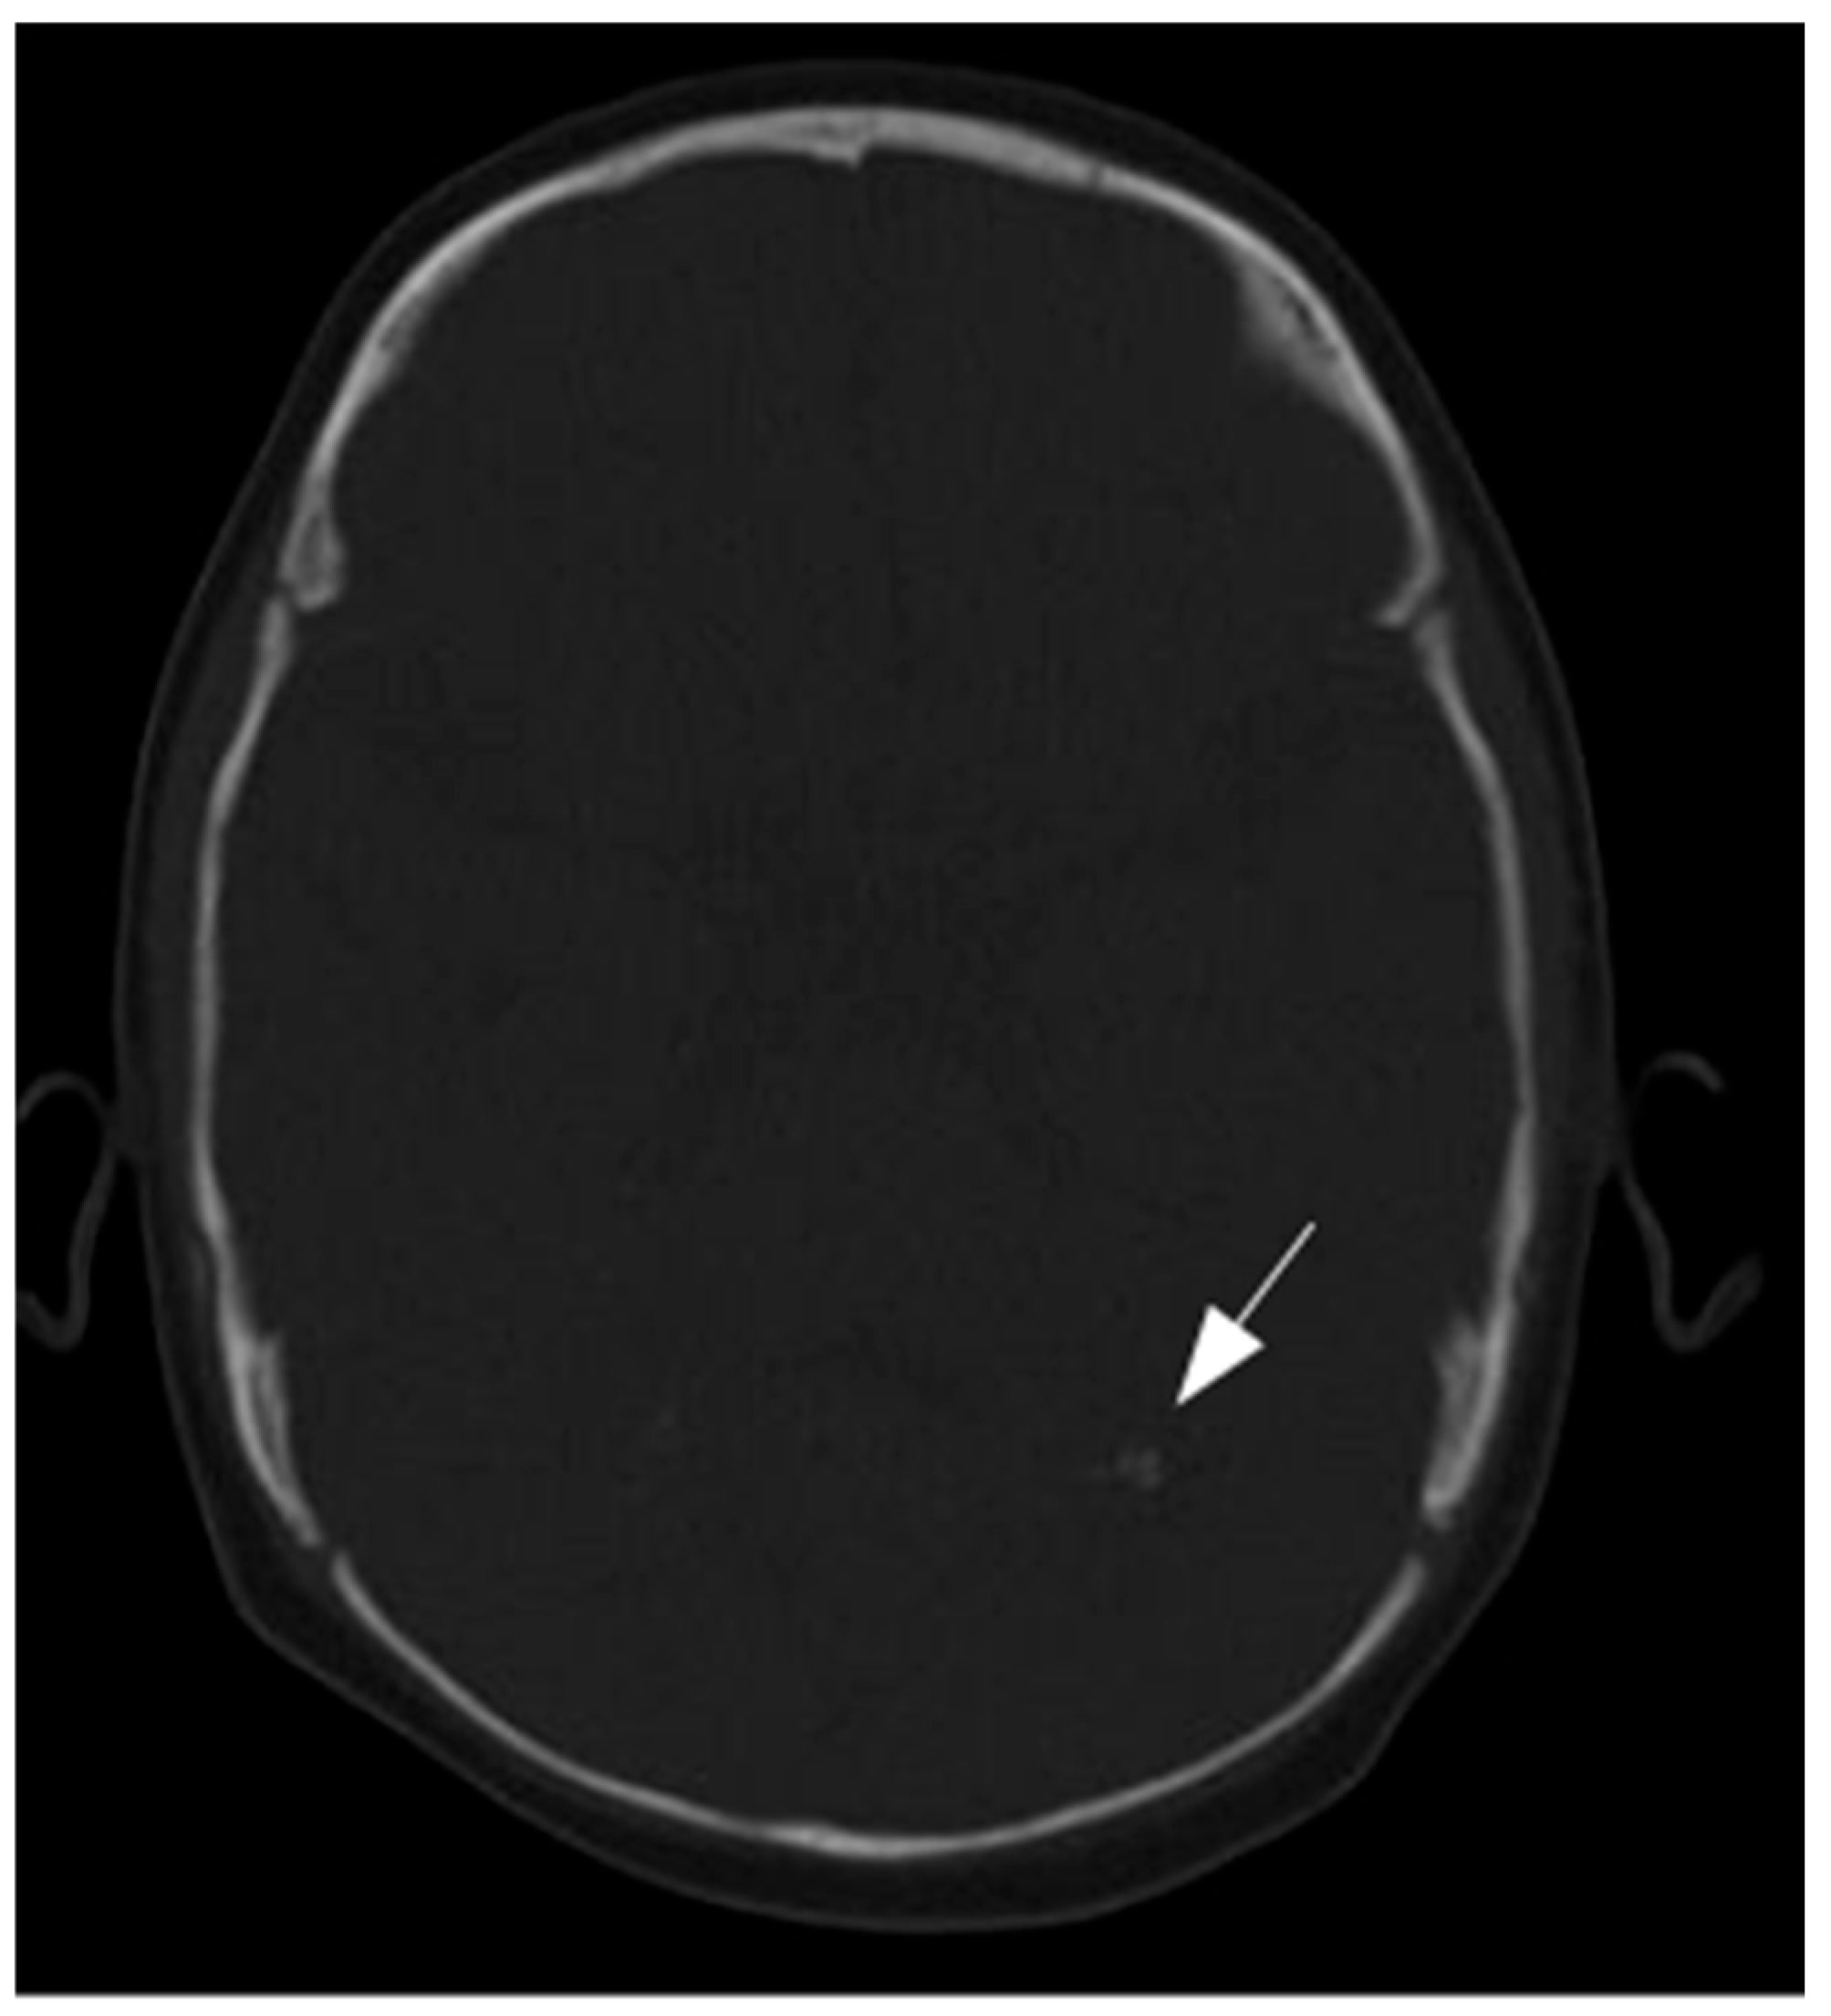

3.2. Results of Imaging Data